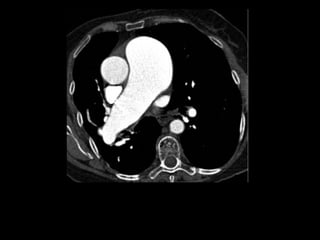

Tomografia computadorizada

Angiotomografia dos vasos pulmonares com TCMD

e reconstruções com filtro de alta resolução;

Mede-se o tronco da pulmonar próximo à sua

bifurcação e lateralmente à aorta ascendente;

Em adultos: até 29 mm;

Sensibilidade: 69-87%;

Especificidade: 89-100%.

TC normal de tórax

Um diâmetro da artéria pulmonar > aorta

ascendente: sensibilidade de 70% e especificidade

de 92% no diagnóstico de HAP;

Achados parenquimatosos: dependem da etiologia

e mecanismo da hipertensão:

Perfusão em mosaico, vidro fosco, espessamento

septal e nódulos centrolobulares.

Derrame ou espessamento pleural, e, em pacientes

com HAP grave, pequeno derrame pericárdico.